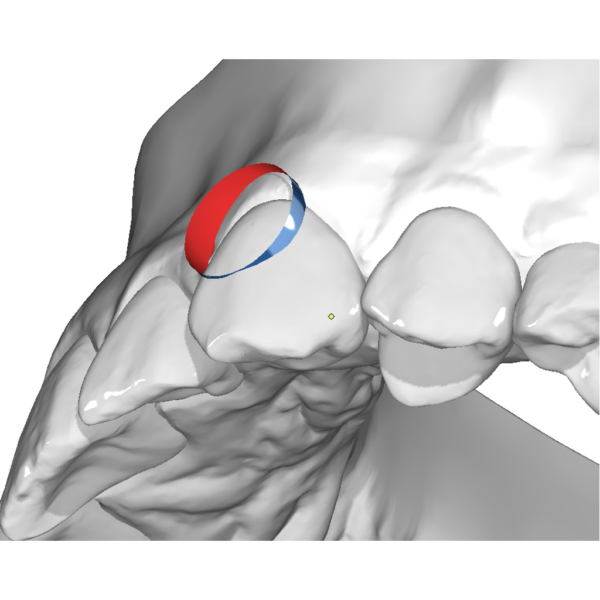

Aligner

Horizontal Attachment

49,00 € excl. VAT Select options This product has multiple variants. The options may be chosen on the product page -